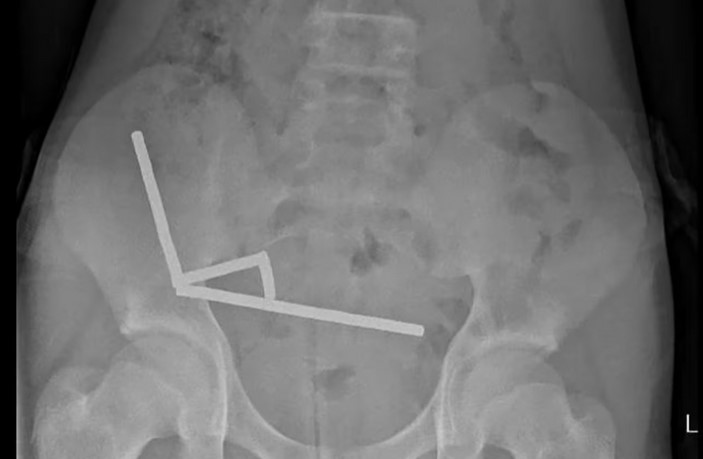

Segundo o relato médico, o adolescente ingeriu entre 80 e 100 ímãs de neodímio, cada um medindo cerca de cinco milímetros por dois. Apesar de pequenos, esses ímãs são extremamente perigosos se ingeridos, pois sua forte atração magnética pode unir diferentes partes do trato digestivo, causando necrose, perfuração ou infecções graves.

O adolescente suportou quatro dias de dor abdominal antes de buscar ajuda. No hospital, exames mostraram que os ímãs haviam se agrupado em quatro cadeias na região inferior direita do abdômen, unindo partes do intestino. Uma cirurgia exploratória revelou necrose por pressão em trechos do intestino delgado e grosso, exigindo a remoção parcial do órgão. Ele permaneceu internado por oito dias antes de receber alta.